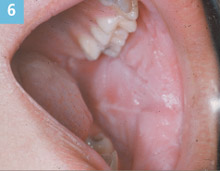

Figure 6. Typical appearance of white sponge nevus in an 11-year-old boy. |

Family history is another valuable component of historical diagnosis. White sponge nevus (Cannon disease, familial white folded dysplasia) is an autosomal dominant inherited condition (if the gene is inherited, there is a 50% incidence that the condition will appear in the carrier’s offspring) characterized by a white, velvety, corrugated folding of the buccal mucosa that is usually bilateral. It is caused by a defect of the normal mucosal keratin. This mother shows the typical clinical appearance of white sponge nevus (Figure 5). Her 11-year-old son also exhibits characteristics associated with the condition but not with the same degree of folding as seen in the mother (Figure 6). It is a benign condition that requires no treatment but because it is an inherited condition, understanding the family history and the mother’s diagnosis prior to seeing the son is helpful.